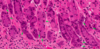

pituitray acinus

This round arrangement of anterior pituitary cells is an acinus.

Normal adenohypophysis is composed of small acini of pituitary cells surrounded by an intact reticulin network (a). In hyperplasia, the acinar architecture is maintained and the reticulin network is preserved, but the acini are increased in size ( b). In contrast, pituitary adenomas are characterized by complete disruption of the reticulin fiber network ( c). Immunohistochemical stains are required to determine the hyperplastic cell population, and these stains will identify the admixed normal cells that contain all of the normal adenohypophysial hormones.